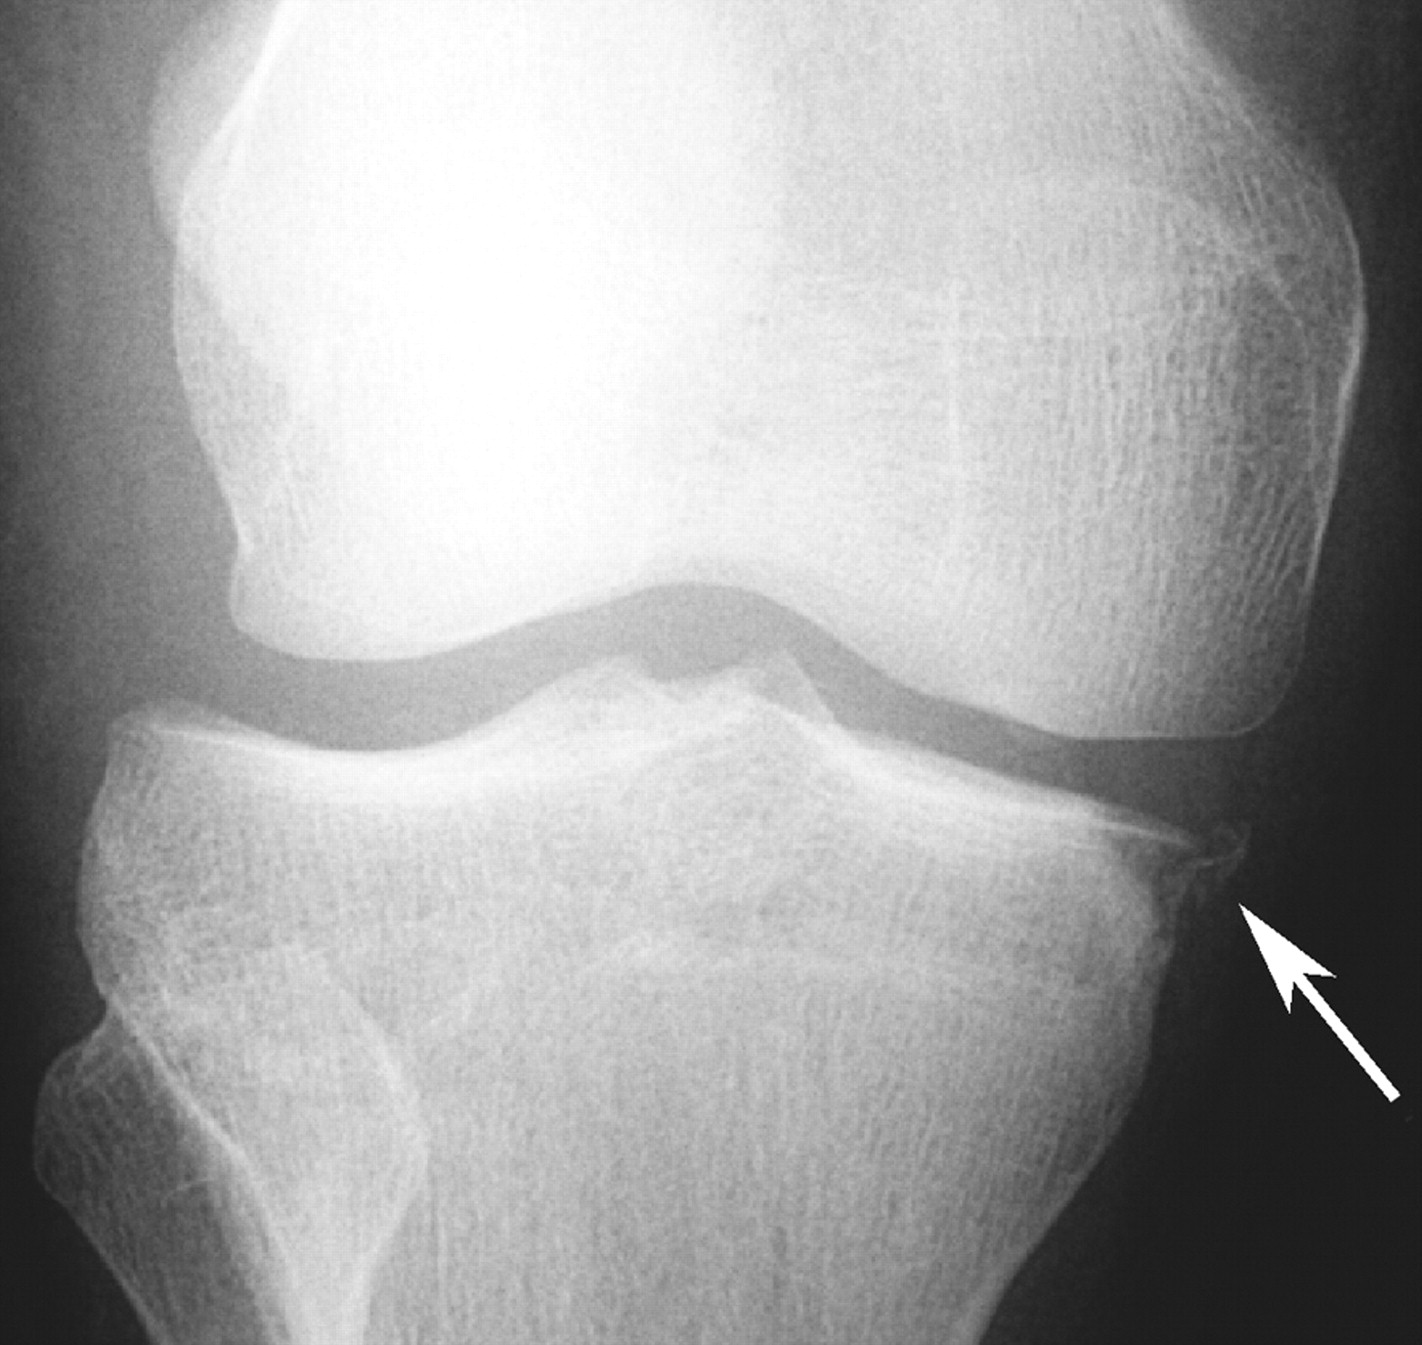

Segond Fracture

This is a very subtle "avulsion fracture of the tibia below the articular margin" caused by traction on the capsular or coronary ligaments. It is not possible to cause this fracture without first rupturing at least one of the major ligaments in the knee.

The classical description1 is limited to the lateral side where associated injuries include:-

Examples in order of increasing subtlety: -